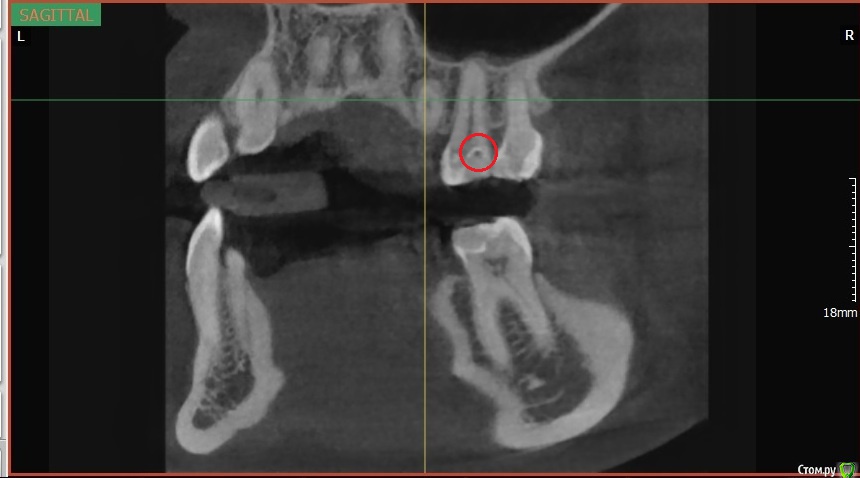

Fatality Опубликовано 12 июня, 2017 Поделиться Опубликовано 12 июня, 2017 Здравствуйте! Возникло 2 вопроса после лечения зубов.Первый вопрос касается зуба 4.6. После чистки камней появилась боль при накусывании на 4.6, при лечении был выявлен глубокий кариес. Зуб почистили, закрыли пломбой, но болевые ощущения уже 2 недели при накусывании не уменьшаются и не уходят (в спокойном состоянии зуб не беспокоит). Прилагаю снимок после лечения (сделан как раз к концу 2й недели), чтобы понять - стоит ли ждать, что неприятные ощущения пройдут или же нужно заново вскрывать и что-то с этим делать. Если нужно покрутить зуб в разных плоскостях, могу сделать и прислать дополнительные фотографии.И второй вопрос касательно пор в пломбировочном материале. Последние несколько месяцев по рекомендации знакомых ходила к одному и тому же стоматологу, и вроде бы все устраивало, но сделала КТ и при расшифровке мне указали на поры в пломбах во всех зубах, которые лечил этот врач (снимок прилагаю, мне обвели красным как раз одну из пор). Объясните, пожалуйста: в чем опасность пор, стоит ли перелечивать эти зубы заново (период, за который они были сделаны - с декабря 2016 по май 2017), и нужно ли менять стоматолога раз такая ситуация повторилась на всех зубах, которые он делал. Ссылка на комментарий

St. Опубликовано 12 июня, 2017 Поделиться Опубликовано 12 июня, 2017 А кто Вам КТ расшифрововал?По приложенному скрину проблем с пломбами не увидела, то что вы приняли за пору наложение в проекции.В нижнем зубе пломба достаточно близко к нерву. По высоте она вам не мешает? Ссылка на комментарий

DmitrySH Опубликовано 12 июня, 2017 Поделиться Опубликовано 12 июня, 2017 Поры в пломбировочном материале, так же как и нарушение прилегания пломбировочного материала на КТ точно диагносцировать не представляется возможным из-за особенностей КТ. На прицельных снимках будет видно. Ссылка на комментарий